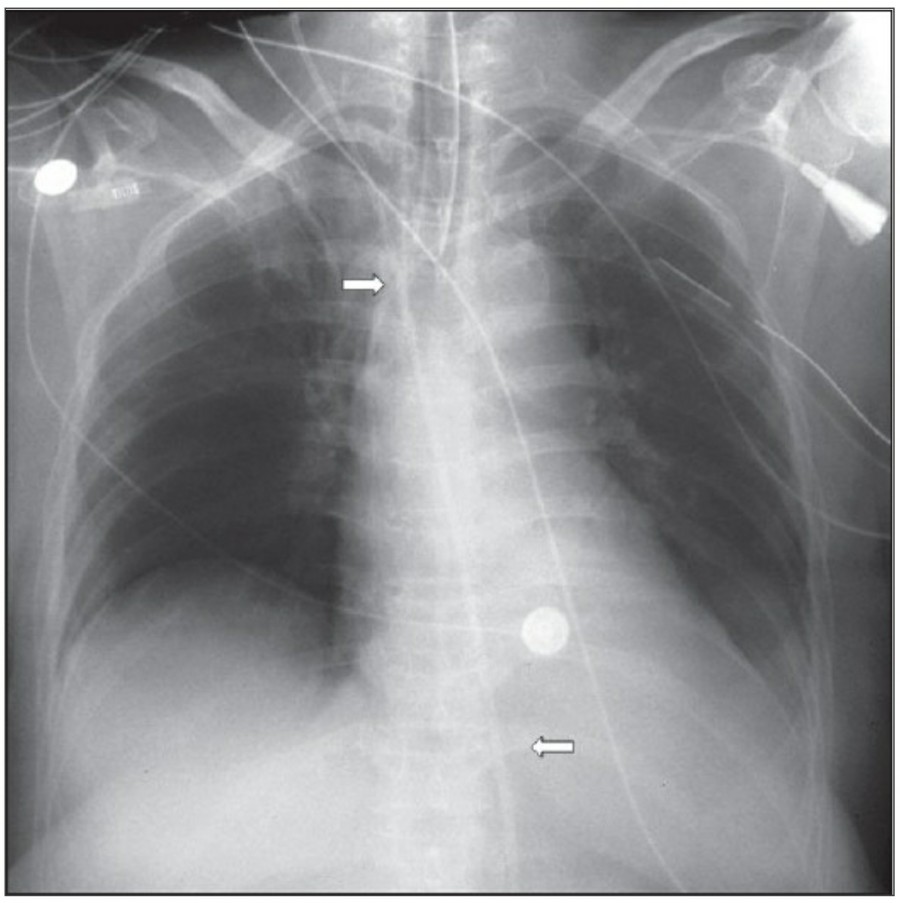

중환자에서 pneumothorax의 진단은 종종 supine radiograph에서 내릴 수 있다. Supine position에서 공기는 anteromedial 방향으로 모이게 되는데, apical air collection이 있을 경우 large pneumothorax가 있음을 시사한다. 공기는 lung과 diaphragm 사이의 subpulmonic location에 trap 되어 있을 수도 있다. 공기가 costophrenic sulcus로 anterolateral extension 될 경우, 이 costophrenic sulcus의 radiolucency를 증가시키는데, 이를 deep sulcus sign이라고 한다. Subpulmonic pneumothorax의 다른 특징으로 diaphragm의 superior surface와 IVC 윗부분이 뚜렷하게 보일 수 있다.

중환자에서 tension pneumothorax의 진단은 매우 힘들다. ARDS와 같은 lung의 병리적인 기전이 lung compliance를 감소시킴으로써 total lumg collapse를 막는다. 또한 tension pneumothorax의 특징인 mediastinal shift가 PEEP으로 인해 나타나지 않을 수 있다. Chest X ray 상에서 tension pneumothorax는 hemidiaphragm의 depression이나 heart border, SVC, IVC의 이동으로 나타날 수 있다.